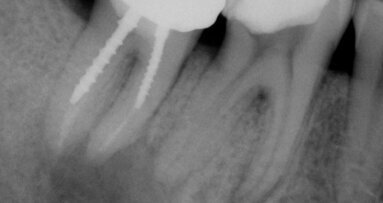

Figs. 2a & 2b : Lorsque les techniques de travail de qualité sont combinées avec une approche biologique de traitement, la guérison est probable. Une réduction substantielle de la taille de cette lésion, au cours d'une période de neuf mois, a eu lieu à la suite d'une bonne isolation, d'une préparation chimio-mécanique minutieuse de canal, intégrant l'irrigation active, puis condensation de l'obturation jusqu'à l'extrémité apicale.